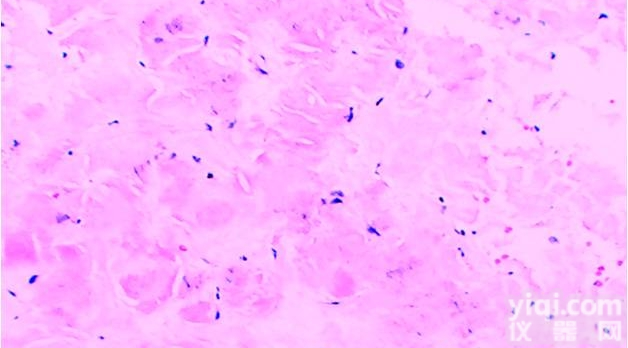

细胞凋亡TUNEL染色:TUNEL细胞凋亡检测 (TUNEL Apoptosis Assay)是一种高敏快速原位观察细胞凋亡的检测方法。对于待检测的细胞或组织样品,经过生物素标记和后续的DAB显色等步骤,即可在普通光学显微镜下观察到凋亡细胞。细胞在发生凋亡时,会激活一些DNA内切酶,这些内切酶会切断核小体间的基因组DNA,基因组DNA断裂时,暴露的3'-OH可以在末端脱氧核苷酸转移酶(TdT)的催化下加上生物素(Biotin)标记的dUTP (Biotin-dUTP),后者与辣根过氧化物酶(HRP)标记的Streptavidin (Streptavidin-HRP)结合,在HRP的催化下通过DAB显色来显示凋亡细胞,从而可以通过普通光学显微镜检测到凋亡的细胞。与流式检测凋亡细胞相辅相成,TUNEL细胞凋亡检测主要是针对组织和细胞,便于观察凋亡细胞的定位和凋亡率,流式FCM凋亡检测则主要是针对培养细胞进行检测,可以准确的判断凋亡率。

凋亡TUNEL染色2.jpg 附件下载 (下载 3 次)

凋亡TUNEL染色1.jpg 附件下载 (下载 4 次)